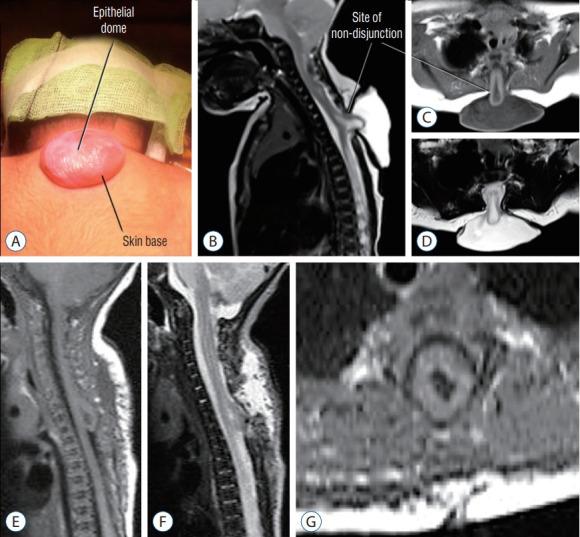

Spinal dysraphic lesions due to focal nondisjunction in primary neurulation are commonly encountered in paediatric neurosurgery, but the "fog-of-war" on these conditions was only gradually dispersed in the past 10 years by the works of the groups led by the senior author and Prof. Kyu-Chang Wang. It is now clear that limited dorsal myeloschisis and congenital spinal dermal sinus tract are conditions at the two ends of a spectrum; and mixed lesions of them with various configurations exist. This review article summarizes the current understanding of these conditions' embryogenetic mechanisms, pathological anatomy and clinical manifestations, and their management strategy and surgical techniques.

由于原发性神经管形成过程中的局灶性不分离导致的脊柱裂病变在小儿神经外科中很常见,但在过去10年中,由资深作者和王宇辰教授领导的团队的工作才逐渐驱散了这些病症上的“战争迷雾”。现在已经明确,有限性背侧脊髓裂和先天性脊柱皮样窦道是同一谱系两端的病症;并且存在各种形态的它们的混合病变。这篇综述文章总结了目前对这些病症的胚胎发生机制、病理解剖和临床表现,以及它们的治疗策略和手术技术的认识。